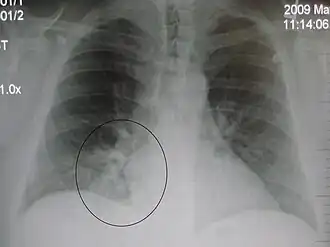

Right upper lobe pneumonia as marked by the circle. -